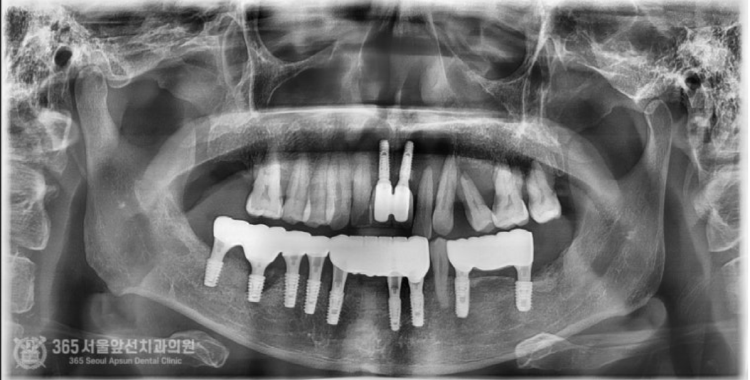

촬영일시: 2024.07.06. 구강스캐너를 사용하여 즉시보철물 제작을 위한 본을 뜹니다. 세상이 정말 편해졌습니다 ㅎㅎ 아래턱 뼈의 밀도가 나쁘지 않았기에 충분한 고정력을 얻을 수 있었고, 환자분의 바람대로 수술 후 즉시 임시치아를 해드릴 수 있었습니다. 촬영일시 : 2024.07.06. 수술 후 임시치아를 바로 연결해드리는 경우, 단단한 음식을 매우 조심하셔야 합니다. 임플란트가 충분히 고정력을 얻었더라도 아직 뼈와 완전하게 골융합되지 않았으므로 강한 저작력이 가해질 경우 임플란트가 빠질 수 있기 때문입니다. 환자분께 이러한 주의 사항을 충분히 드리고 주기적으로 체크하며 관리해드렸습니다ㅎㅎ 대략 4개월 정도 기간이 지난 후 최종보철물로 교체하여 완성해드렸습니다. 즉시 임시치아를 해드릴 경우 몇몇 임플란트가 빠질 수 있으나, 다행히 환자분께서 조심조심해서 식사를 해주시고 관리를 열심히 해주셔서 단 한개의 임플란트도 빠지지 않고 마무리해드릴 수 있었습니다 ^^ 촬영일시 : 2024.11.02. 완성 후 구강 내 모습입니다. 아래턱 치료가 마음에 드셔서 그런지 얼른 윗턱 임플란트 치료도 받고 싶어하십니다 ㅎㅎ 촬영일시: 2024.11.02. 오늘은 뼈이식을 동반한 발치즉시 임플란트 수술 및 즉시임시치아 제작까지 해드렸던 환자분의 증례를 공유해보았습니다. 뼈의 양이나 뼈의 질에 따라서 즉시임시치아는 불가능할 수도 있으니 의료진과 충분한 상의하에 만족스러운 치료를 받으시면 좋겠습니다 ㅎㅎ 이상, 도화역치과 365서울앞선치과였습니다. 더 좋은 증례로 찾아뵙겠습니다! ※ 365서울앞선치과의원의 모든 포스팅은 각 진료과 의료진이 직접 작성합니다. 365서울앞선치과의원 블로그의 임상 케이스 게시물은 환자분께 의학적으로 정확하고 상세한 정보를 드리기 위해 각 진료과 의료진이 직접 작성하며, 모든 증례 사진은 본원 의료진이 직접 시술한 증례를 촬영한 것으로, 의료법 제23조, 제56조에 의거하며 환자분의 동의를 얻어 포스팅에 사용하였습니다. 또한 해당 케이스는 본 환자분의 치료 결과이며, 환자 상태에 따라 치료의 결과는 달라질 수 있습니다. |